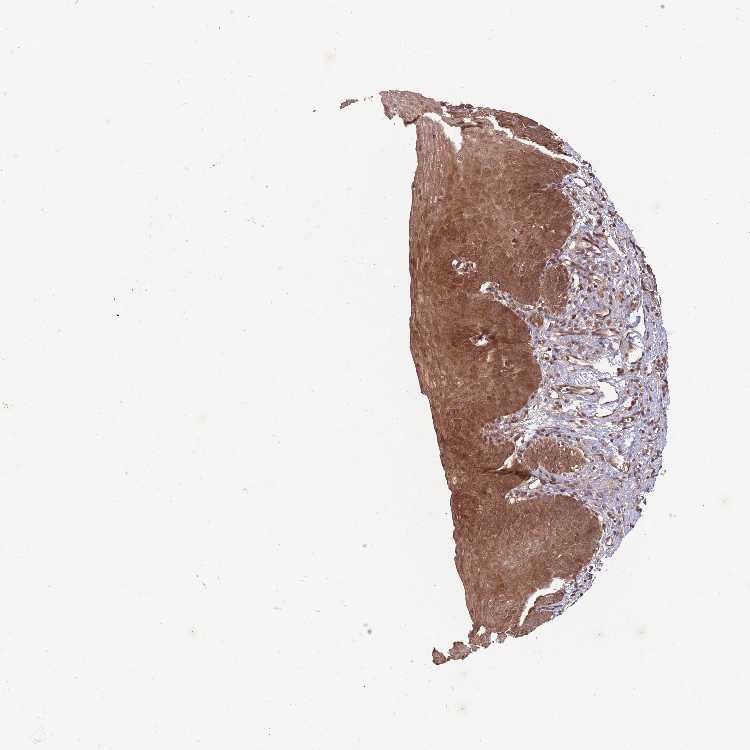

ESOPHAGUS - Antibody stainingi

Antibody staining in the annotated cell types in the current human tissue is reported as not detected, low, medium, or high, based on conventional immunohistochemistry profiling in selected tissues. This score is based on the combination of the staining intensity and fraction of stained cells.

Each image is clickable and will lead to virtual microscopy that enables deeper exploration of all samples and also displays staining intensity scores, fraction scores and subcellular localization as well as patient and tissue information for each sample.

Antibody HPA055548Antibody HPA056074Antibody CAB033838

Squamous epithelial cells HighNot detectedMedium